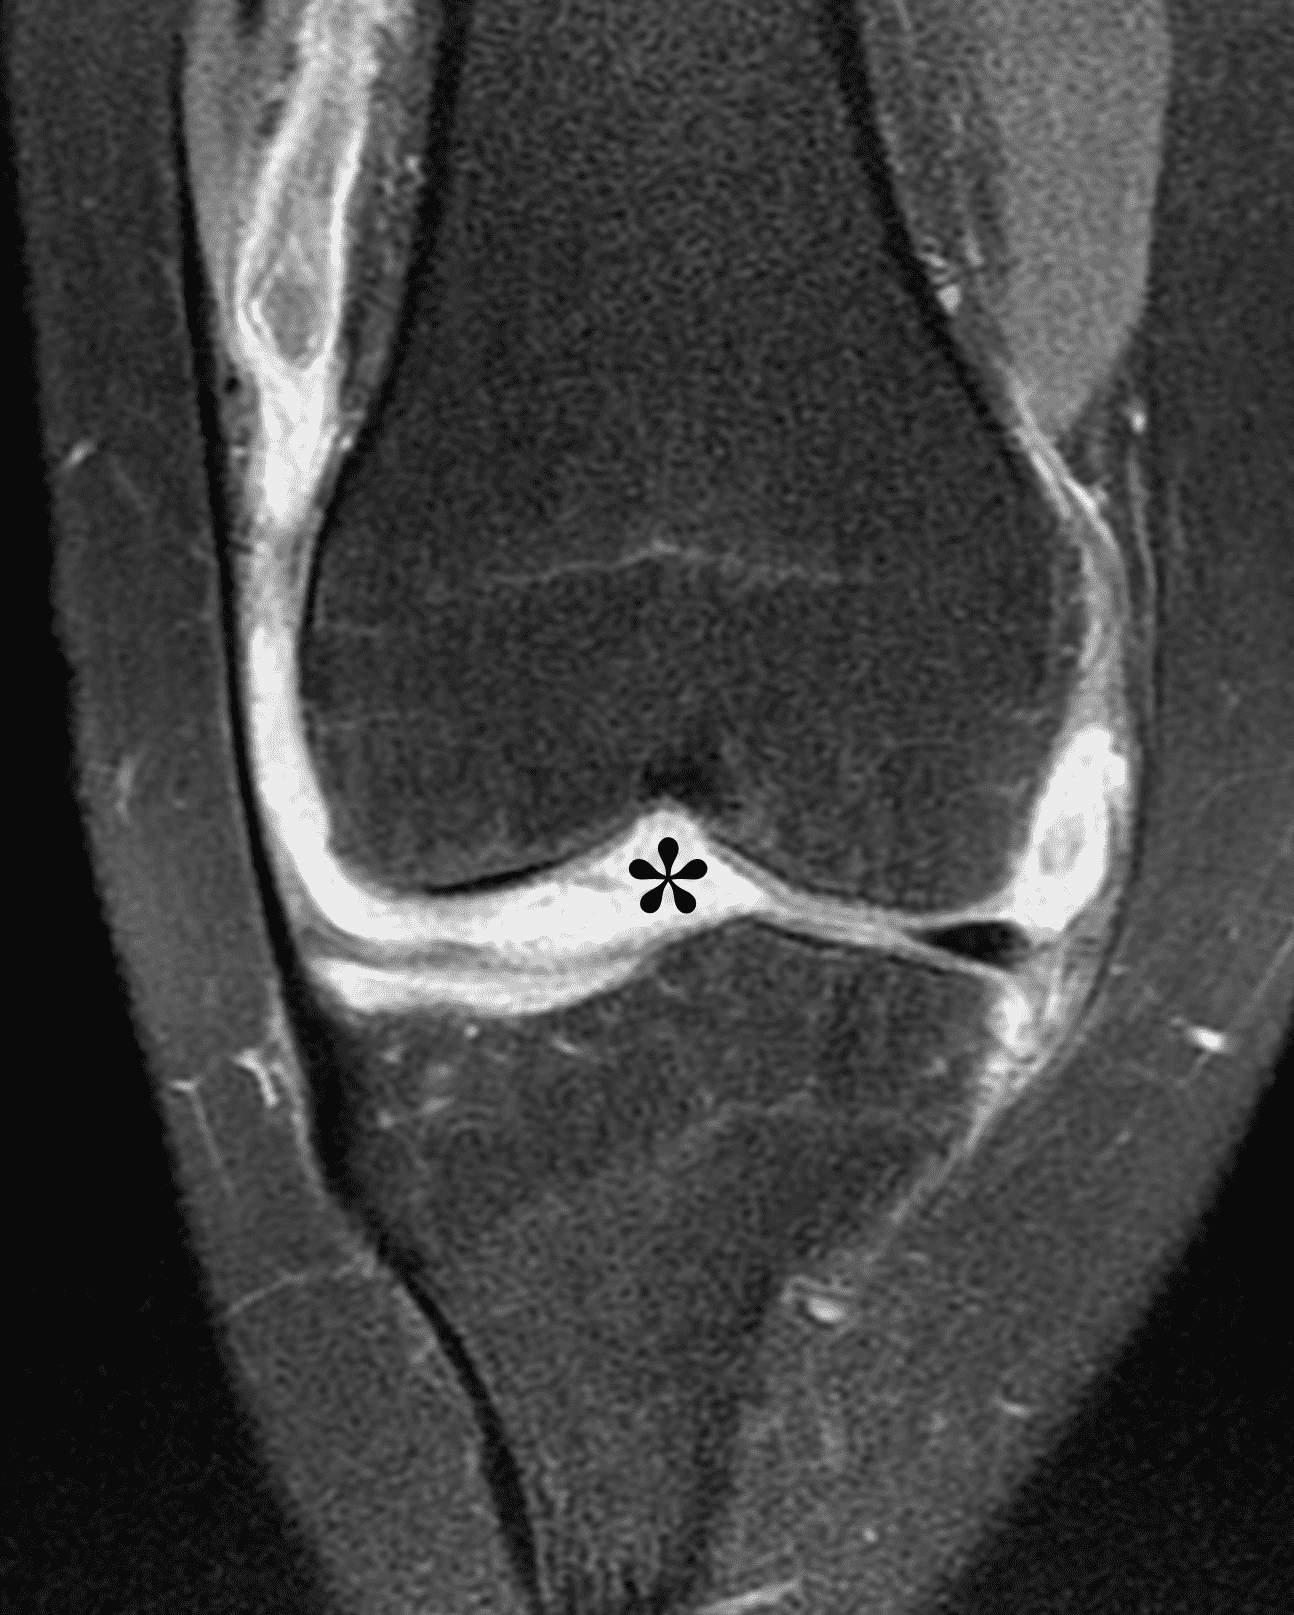

Figure 2: (2A) The coronal image shows a large effusion and severe hypertrophic synovitis (asterisks) in the knee. (2B) On the sagittal image the hypertrophic synovium (asterisks) involves the suprapatellar and infrapatellar recesses as well as the anterior and posterior intercondylar notch. A reactive lymph node (arrow) is present in the popliteal fossa. (2C) The axial image demonstrates myositis (arrows) involving the popliteus and peroneus longus muscles. Note the preserved articular cartilage, lack of erosions, and the absence of subcutaneous or marrow edema.

The causative spirochete invades the synovium, triggering a host inflammatory response that leads to synovial hypertrophy and inflammation, resulting in the characteristic clinical symptoms and imaging findings associated with Lyme arthritis.2 Common MR findings associated with Lyme arthritis include synovitis, joint effusion, popliteal lymphadenopathy, and myositis predominantly involving the popliteus (Figure 4).2,3,9 In contrast to acute septic arthritis due to more common bacteria, subcutaneous edema, marrow edema, erosions, and osteomyelitis are uncommon (Figure 4C).